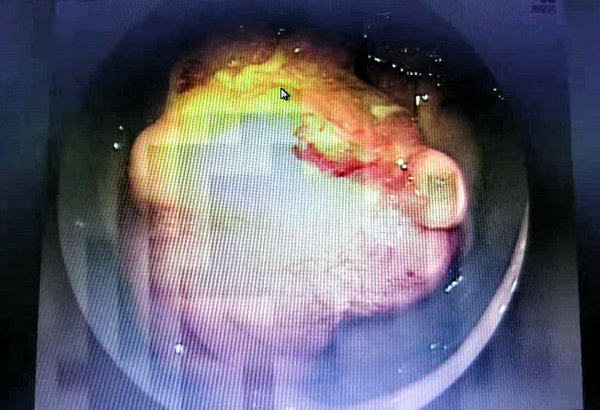

53岁的李先生因间断腹痛1个多月,最近1天突然腹痛加重,无法正常生活,于是在家人陪同下急诊入院,经消化道造影、纤维结肠镜检查发现,距肛门约60厘米处有一隆起病变,边界不清楚,表面污秽肠腔明显狭窄;距肛门30厘米处发现一个大小约2.0X1.0厘米息肉,表面分叶、糜烂。